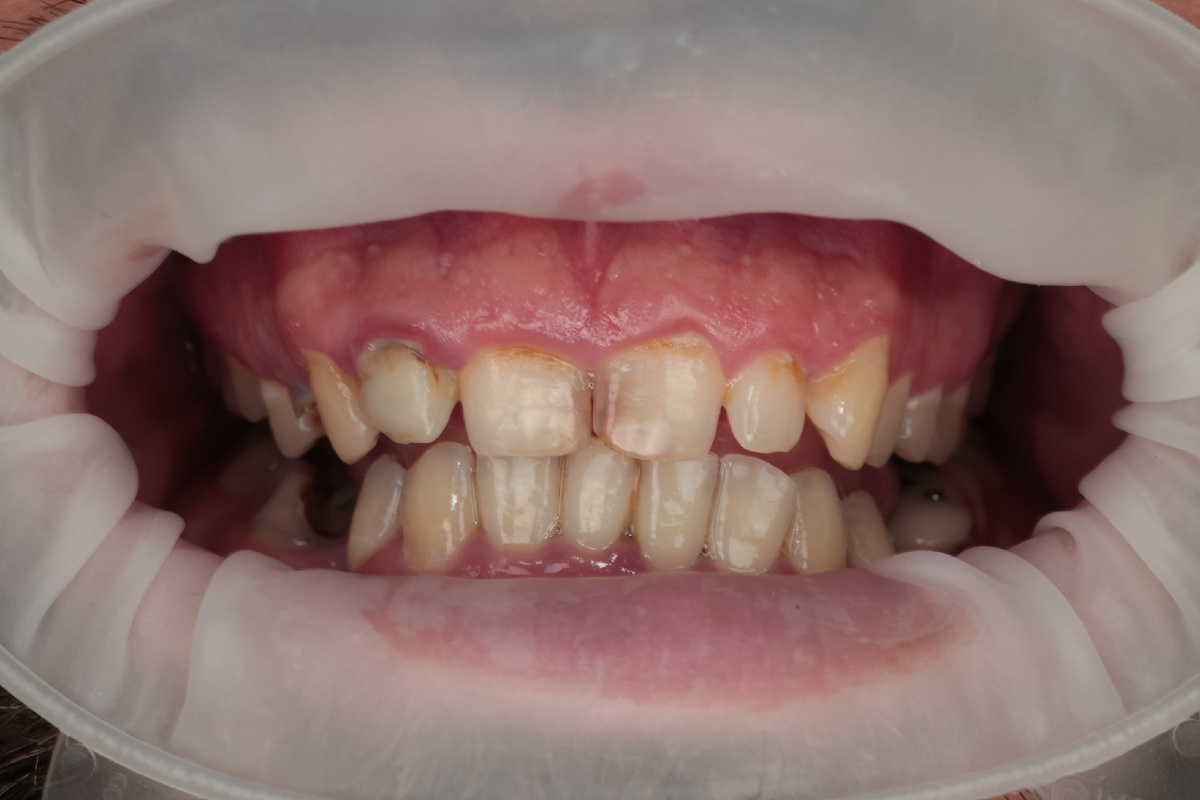

Зубы без ухода 20 лет

Пусть, наш пациент будет Петром (имя изменено). Когда Петр пришел, его лицо выражало смесь отважности и стыда. Он долго колебался перед принятием решения, записаться на прием или нет. В течение двух десятилетий он избегал стоматологов, полагая, что проблемы с зубами не столь важны. Однако улыбка с каждым днем не становилась краше, спутница Петра помогла сделать первый шаг на пути к здоровой улыбке.

Самое интересное, что Петр не жаловался на боль, все отболело уже давно, на данный момент, это просто некрасиво и не функционально, жевать неудобно.

Каждый первичный пациент, который приходит в нашу клинику, первостепенно направляется на КТ (компьютерную томограмму), без нее не проходит консультация. И конечно, фотопротокол, чтобы наглядно, вместе с пациентом, видеть проблему.

После полученных снимков и фотографий, я преступила к составлению плана лечения, выделяя главные проблемы. Важной задачей, на мой взгляд, было наладить навыки гигиены в домашних условиях, привить любовь в дополнительным средствам гигиены.